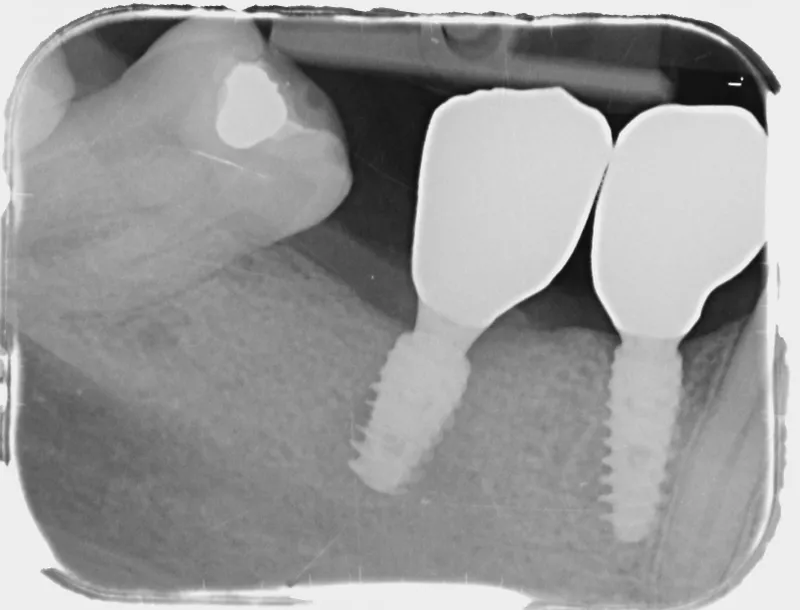

9. Panoramic radiograph taken on the day of implant placement.

9